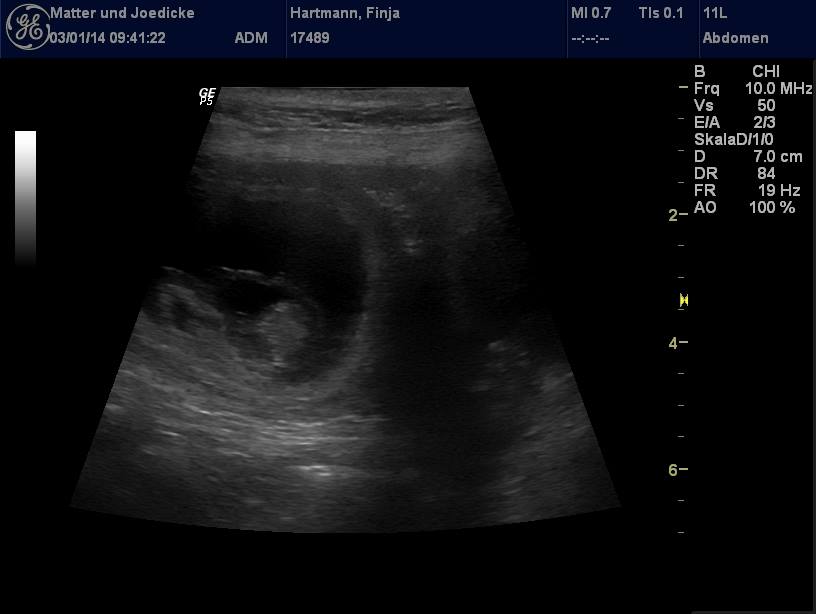

Bei der ersten Ultraschalluntersuchung wurden ca. 7 Welpen gesehen: